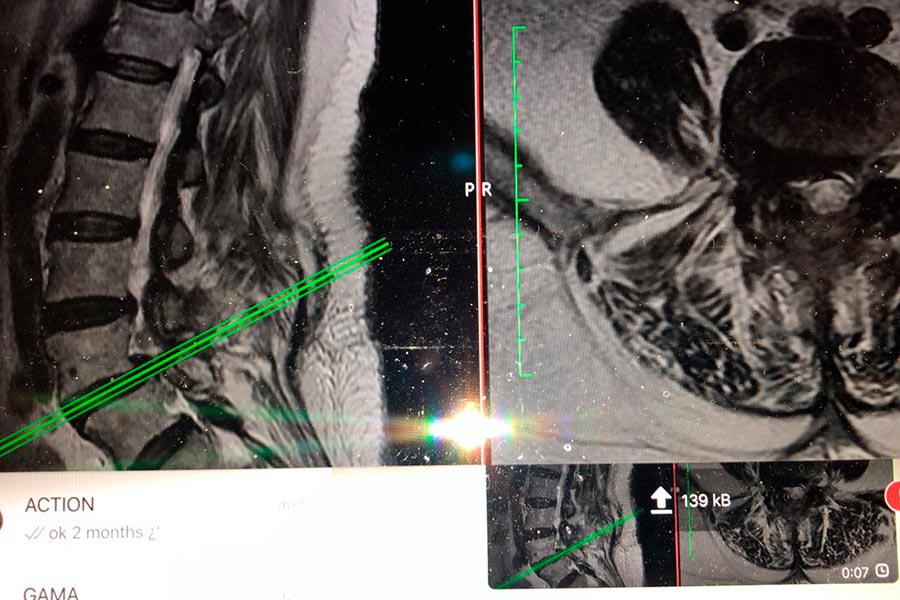

Caso clínico de Hernia en el disco L5S1 lateralizada

Hernia discal lateralizada

En este caso, el Doctor Elgeadi se encarga del tratamiento, con una tecnica de cirugía mínimamente invasiva, de localizar y extraer una hernia discal, de pequeño tamaño en la L5S1.

A pesar de que el tamaño de la hernia es bastante pequeño, el paciente sufre molestias en el tren inferior, con dificultades a la hora de caminar o hacer esfuerzos con las piernas.

hernia-discal-l5si-lateralizada